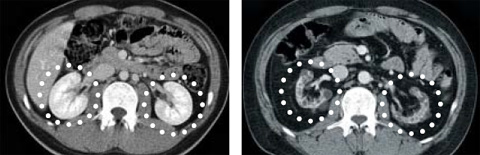

정상 신장(왼쪽)과 투석을 받고 있는 당뇨병성 만성신부전증 5기 환자의 신장 CT(컴퓨터단층촬영) 사진. 혈당 때문에 여과 기능을 거의 못하게 되면서 크기가 작아졌다. /성빈센트병원 제공